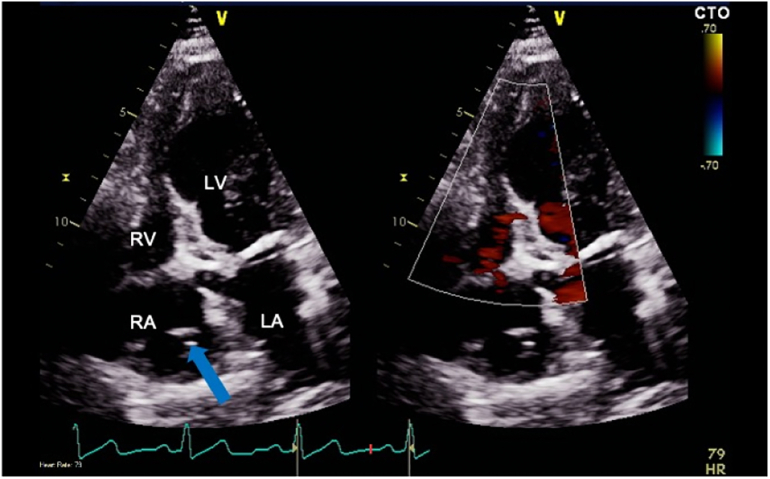

Further cardiac imaging with a transthoracic echocardiogram (TTE) revealed a floating foreign body in the RA extending caudally into the cranial end of inferior vena cava (IVC) as shown in Fig. 2 and Video 2. A computed tomography (CT) scan of the chest similarly depicted a foreign body in the right heart without evidence of pulmonary emboli (Fig. 3).

Fig. 2.

Transthoracic echocardiogram on apical four-chamber view. A foreign body in right atrium extending caudally into the cranial end of the inferior vena cava.

LA, left atrium; LV, left ventricle; RA, right atrium; RV, right ventricle.